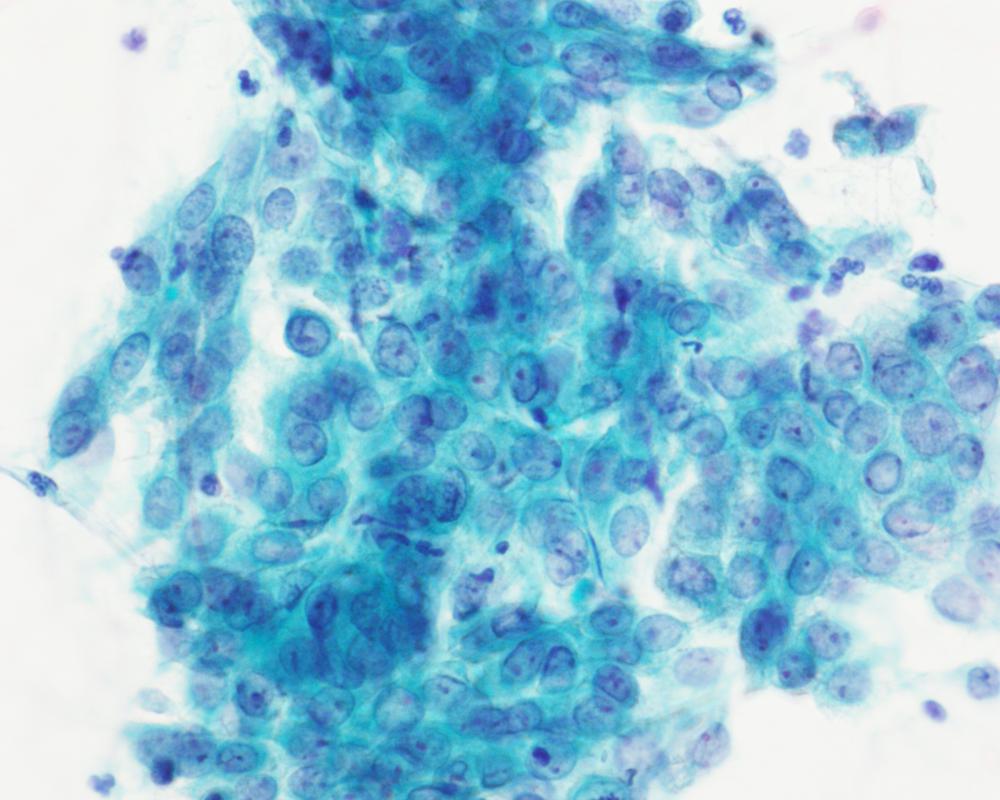

第36回日本臨床細胞学会九州連合会学会(大分)スライドカンファレンス症例4

種別:体腔液

出題:宮崎県立宮崎病院 病理診断科 丸塚 浩助

| 年齢 | 50代後半 | 性別 | 女性 |

|---|---|---|---|

| 採取部位 | 腹水 | 採取方法 | 穿刺 |

| 検体処理法 | 塗抹及びLBC |

臨床所見

<既往歴>

特記なし

<現病歴>

2ヶ月前頃より腹部膨満・下腿浮腫を自覚し、当院産婦人科に紹介受診。MRIにて著明な腹水と骨盤腔内を占める腫瘤が認められ、癌性腹水を伴う卵巣癌との臨床診断で腹水穿刺細胞診が行われた。

化学療法後開腹手術を行ったが、びまん性腹膜播種を認め、腫瘍切除のみ行われた。腫瘍はS状結腸腸間膜に存在し、卵巣・子宮は正常外観であった。

| 正解 | 5.炎症性筋線維芽細胞肉腫 |

▼選択肢及び投票結果

| 1.卵巣漿液性腺癌 | 5件 | (7.8%) | |

| 2.腹膜中皮腫 | 3件 | (4.7%) | |

| 3.消化管間質腫瘍 | 1件 | (1.6%) | |

| 4.未分化大細胞リンパ腫 | 42件 | (65.6%) | |

| 5.炎症性筋線維芽細胞肉腫 | 13件 | (20.3%) | |

| 投票総数 | 64件 | (100%) |